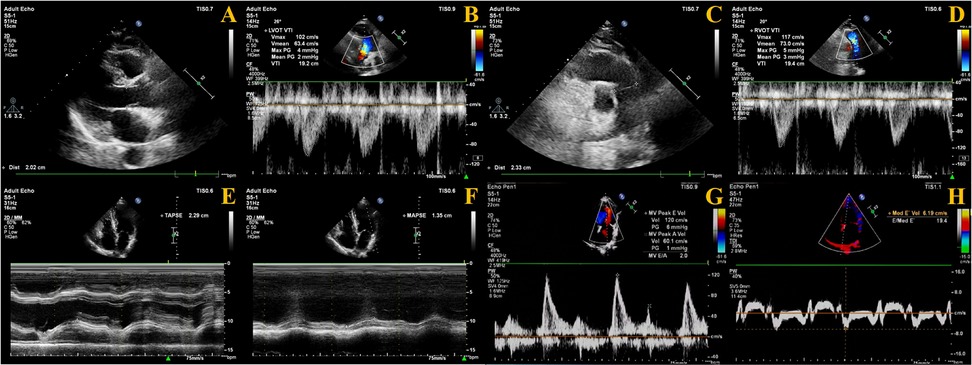

The velocity time integral (VTI) of both the LV outflow tract (LVOT) and RV outflow tract (RVOT) must be measured. Using color Doppler mode, blood flow from the LVOT toward the aorta and from the RVOT toward the pulmonary artery was visualized. The sample line was aligned with the direction of blood flow, and pulsed-wave Doppler mode was used to acquire images for measuring LVOT-VTI and RVOT-VTI, respectively. The diameter of the LVOT and RVOT was measured at the aortic valve annulus and pulmonary valve annulus, respectively. The fomula as follows (

Figure 2):

Cross-sectional area (CSA): CSA = π × (diameter/2)2.

Left ventricular stroke volume (LVSV): LVSV = (VTI × CSA) of LVOT.

Right ventricular stroke volume (RVSV): RVSV = (VTI × CSA) of RVOT.

The difference between RVSV and LVSV is expressed as Delta SV (ΔSV): ΔSV = RVSV—LVSV.

Figure 2

Measurement methods of echocardiography. (A) LVOT diameter measurement; (B) LVOT-VTI measurement; (C) ROVT diameter measurement; (D) RVOT-VTI measurement; (E) TAPSE measurement; (F) MAPSE measurement; (G) E velocity measurement; (H) Septal e′ measurement.

Regarding cardiac coupling ultrasound parameters, ΔSV represents the difference in stroke volume between the RV and LV per cardiac cycle. Based on the study by Zhang et al. (12), we selected TAPSE and MAPSE—parameters reflecting the longitudinal systolic function of the RV and LV, respectively—and calculated their ratio (TAPSE/MAPSE) (Figure 2).